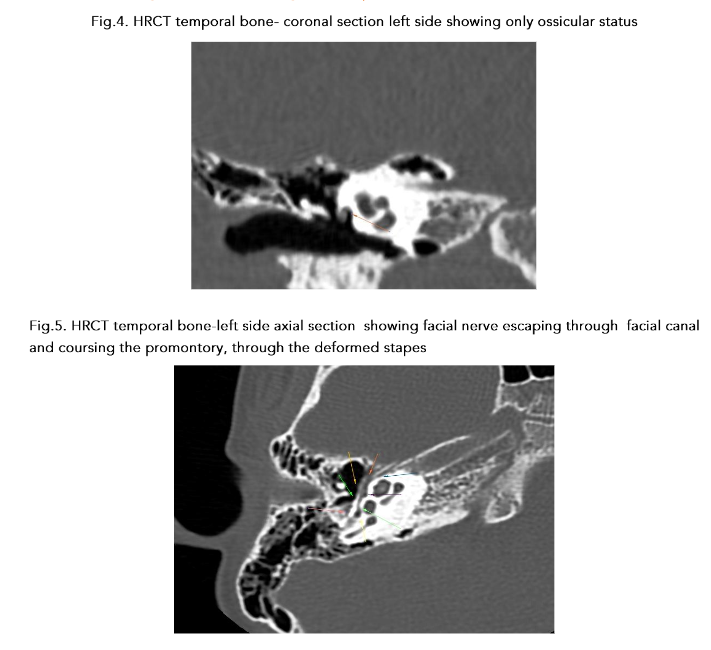

Otoendoscopy and diagnostic nasal endoscopy were normal. High resolution computed tomography (HRCT) of the temporal bone showed agenesis of the right stapes and dysplastic left stapes with aberrant course of the facial nerve (Fig. 3, 4 & 5).

A sound radiological knowledge with study of the HRCT on the console helps in being prepared for the surgery, which may be beneficial in correcting the deformity benefitting the patient. The principal role of the radiologist in case of exploratory tympanotomy is to guide the surgeon by predicting difficulties which may be encountered during surgery. High resolution computed tomography (HRCT) of the temporal bone is the investigation of choice before surgery, but it is not performed on a routine basis for uncomplicated cases. In a study, Zeifer et al. reported that HRCT enables preoperative diagnosis of anomalous course of the facial nerve as well as absence of the oval window. This is likely due to advancements in CT imaging, allowing high spatial resolution and image quality.